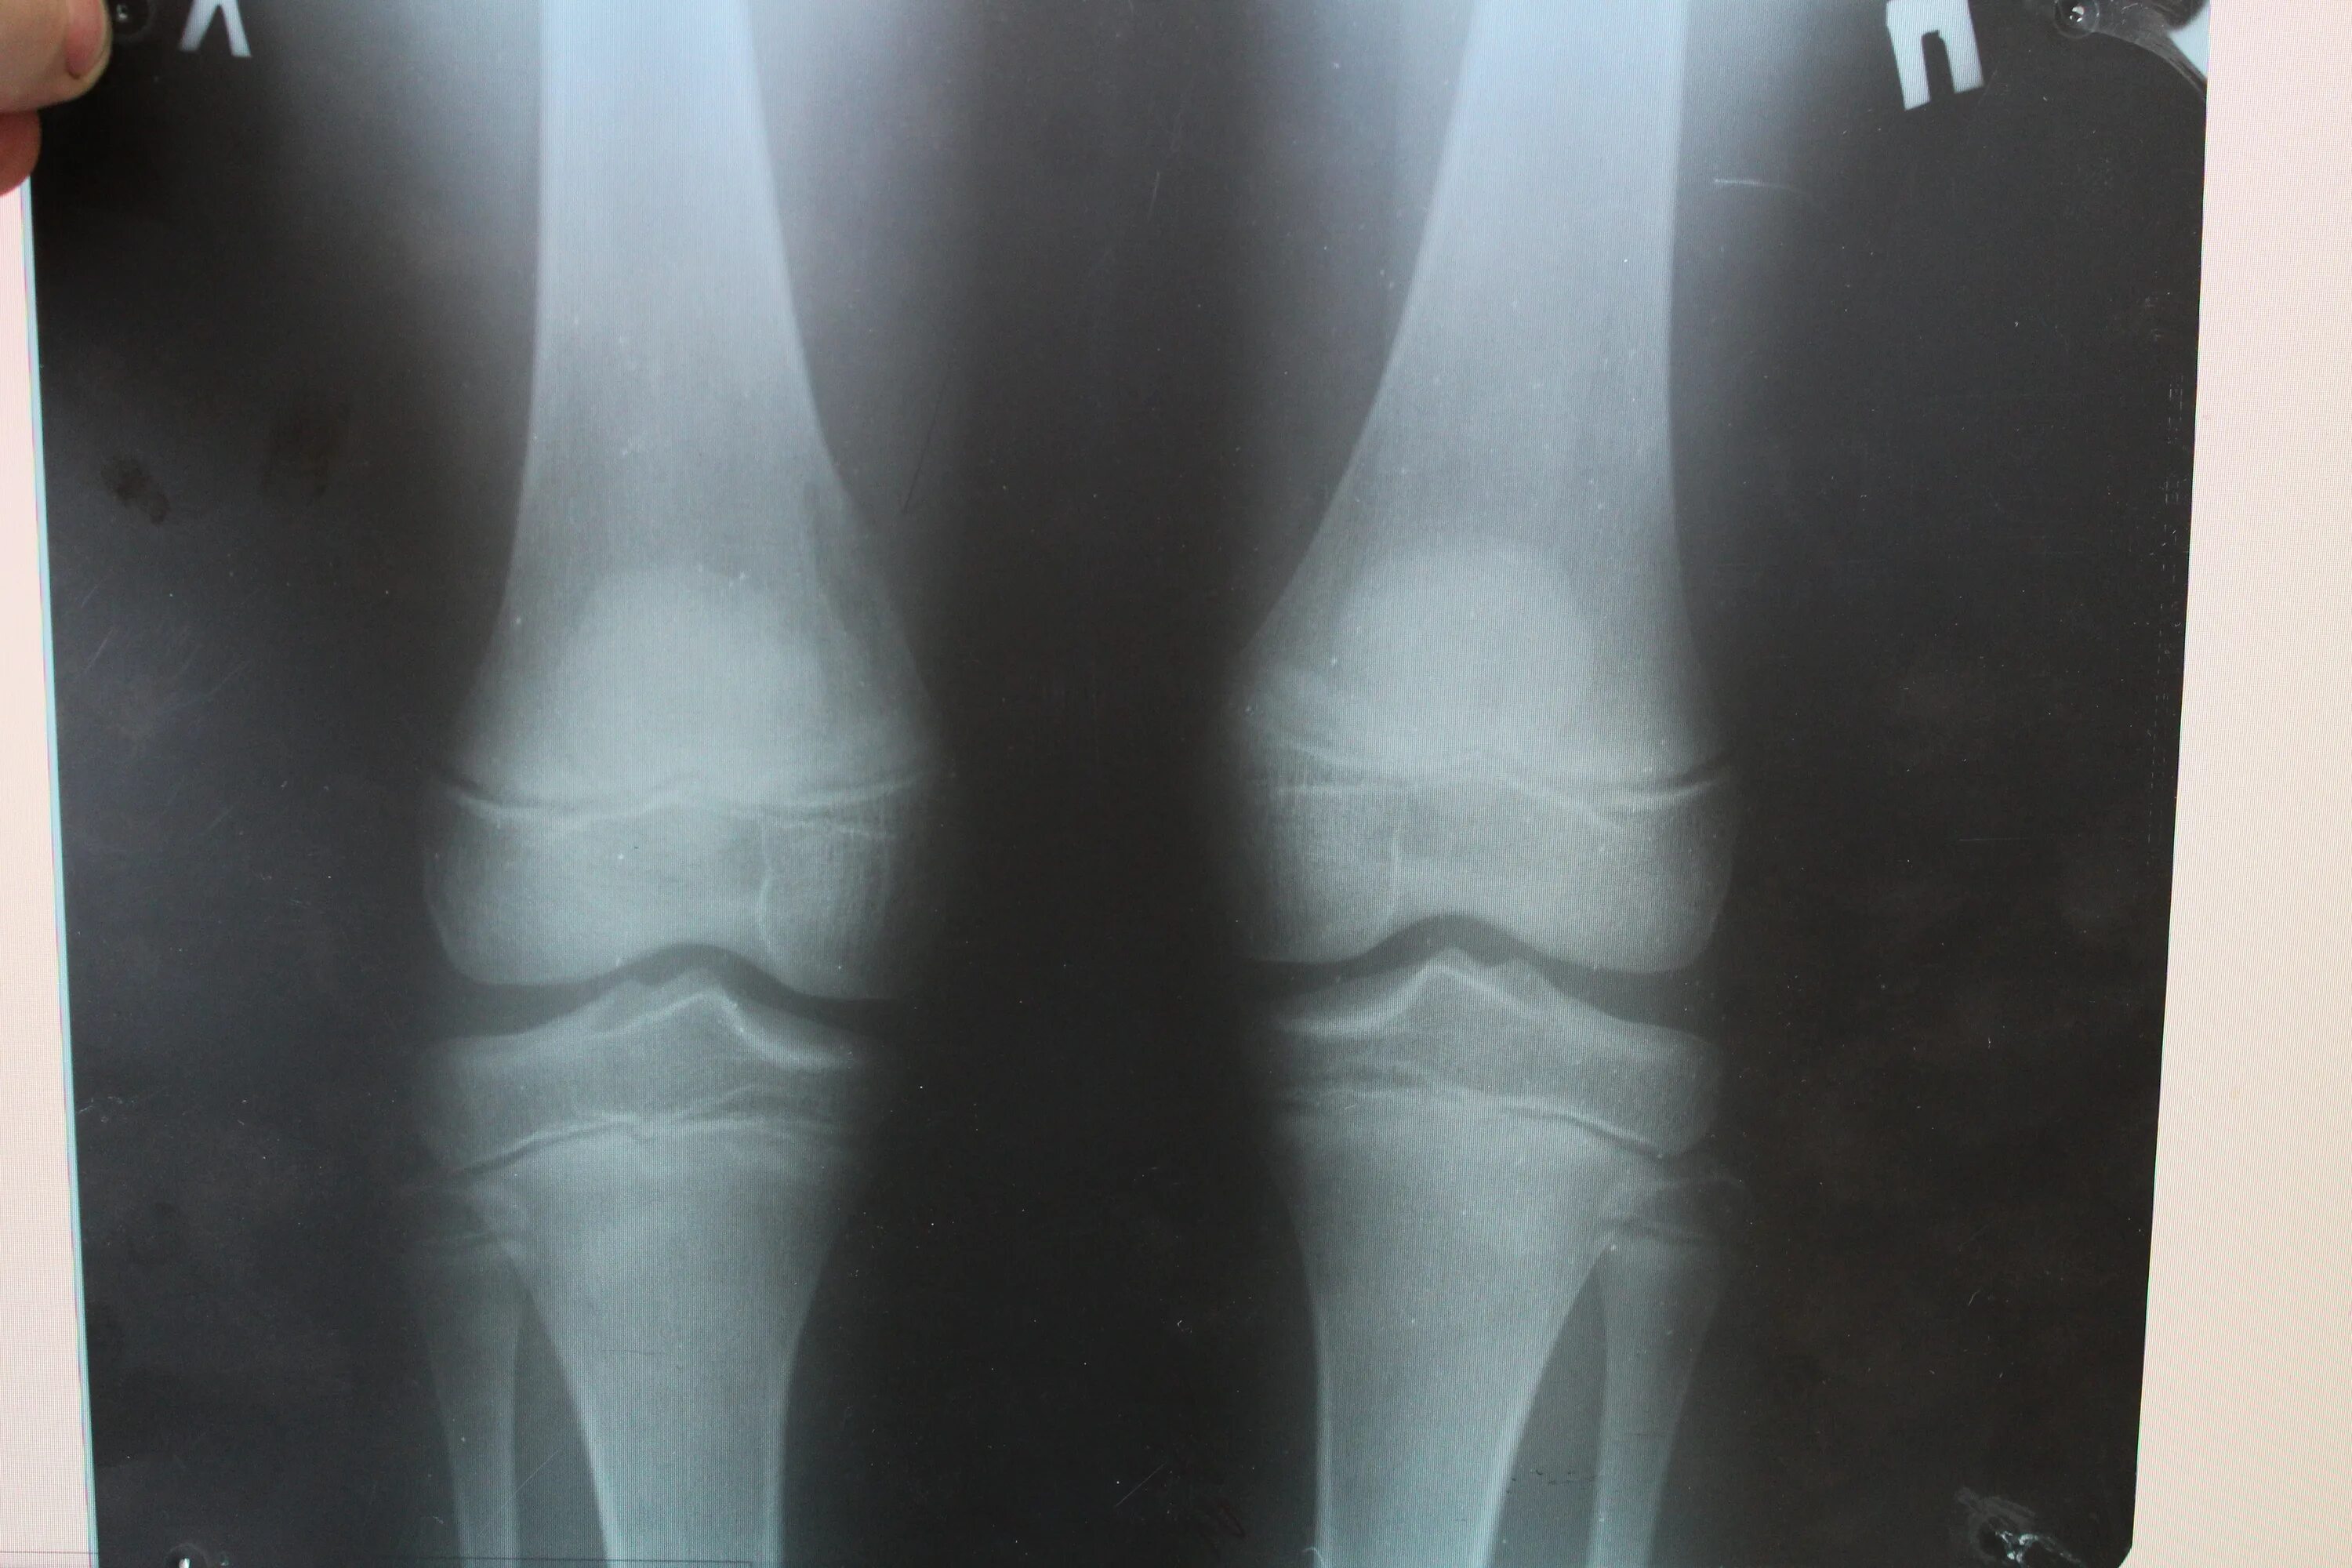

Дисплазия 7 лет